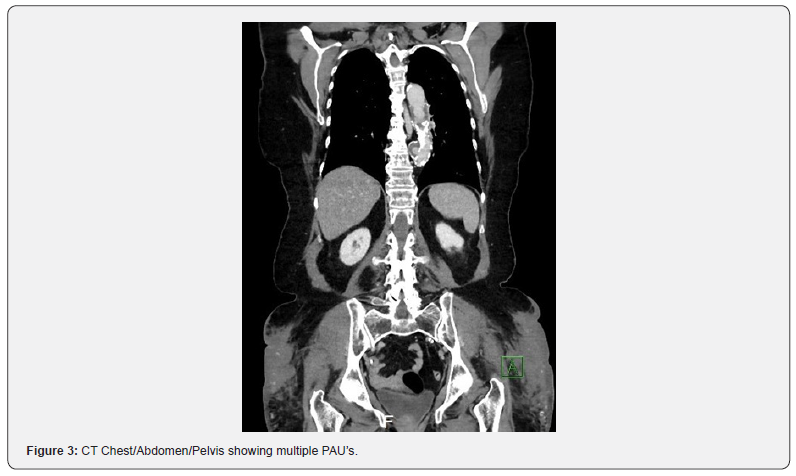

Case Presentation: A patient with multiple comorbidities including coronary artery disease and peripheral artery disease (Rutherford 4 symptoms bilaterally) presented to the emergency room with chest pain and dyspnea on exertion. The patient was found to have a 3.5 cm descending thoracic aortic aneurysm, multiple penetrating aortic ulcers (PAU’s) within the descending thoracic aorta which was felt to be the cause of her chest pain along with heavily calcified occlusive aorto-iliac disease. The patient was deemed high surgical risk for open repair and the patient’s severe calcific distal aortic stenosis and bilateral severe ostial iliac stenosis was deemed a barrier for endovascular repair. Therefore, the patient was successfully treated with kissing balloon lithoplasty for lesion preparation of the heavy calcification and placement of an endovascular stent graft (EVAR) in the distal aorta, which ensured a safe conduit for thoracic endovascular aortic repair (TEVAR) procedure.

73-year-old female with past medical history of non-insulin dependent diabetes mellitus, hypertension, hyperlipidemia, coronary artery disease (stent to the distal and mid right coronary artery [RCA]), and peripheral artery disease (Rutherford 4 symptoms bilaterally) presented to the emergency department for sudden onset chest pain and dyspnea on exertion. Patient had multiple previous admissions with similar complaints for chest pain and had multiple biochemical assays and imaging studies including coronary angiography to evaluate for coronary artery disease, which were negative. During this admission, the patient underwent CT angiography which demonstrated a 3.5 cm descending thoracic aortic aneurysm, multiple PAU’s within the descending thoracic aorta, a severely calcified distal aortic stenosis and bilateral severe ostial iliac stenosis (Figures 1-3). Given recurrent admissions and negative cardiac work up, the thoracic penetrating aortic ulcer was thought to be the etiology of her chest pain. There was concern regarding the treatment of the thoracic penetrating ulcer as the patient was ultimately deemed high-risk for surgical repair and there was no clear conduit to get to the thoracic aorta by an endovascular approach due to the severe distal aorto-iliac occlusive disease. After discussions between vascular surgery and interventional cardiology, a decision was made to proceed initially to treat the severe distal aorto-iliac stenosis with a bifurcated stent graft to ensure a clear endovascular passage to ultimately treat the thoracic aortic disease. Calcium, plaque modification and possible stenting was deemed a necessary and warranted strategy for lesion preparation to help facilitate the large TEVAR delivery system. Lack of proper lesion preparation of heavy calcificed lesions can lead to complications such as dissection, perforation, inability to advance the device, and ultimately failure of the procedure. Intravascular balloon lithoplasty has shown favorable results in recent clinical experience in the realm of structural heart disease in order to complete transcatheter aortic valve replacement (TAVR) procedures therefore this method of lesion preparation was chosen for this case [7,8]. Intravascular lithoplasty functions by incorporating lithoplasty emitters within an angioplasty balloon, such that sonic pressure waves drive through surrounding tissue selectively fracturing vascular calcium within the vessel wall, thus purportedly altering vessel compliance and permitting vessel dilation at relatively low pressures. Other methods to prepare the lesions such as balloon angioplasty or atherectomy were considered but was believed that it was inadequate and may leave residual stenosis and unsatisfactory result within the artery.